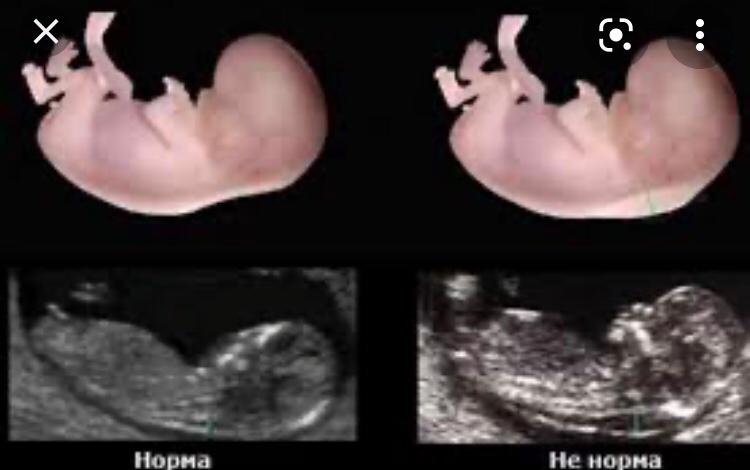

Сабаққа кіріспе Суретті қарап, бүгінгі сабағымызды ашып алайық

Дескриптор: - аурулардың хромосома жиынтықтарын аңықтайды; - оларды кариотиптерімен сәйкестендіреді. Бағалау: Мұғалім мадақтауы Топтық жұмыс Суретті пайдаланып оқушылар түсіндіреді Iтоп

Дескриптор:

Бағалау: «Екі жұлдыз бір тілек» топтар бір бірін бағалайды Бұл тапсырмалар оқушыларға сабақтың тақырыбын ашады, оқушылар аурулардың түрін зерттейді. Ұсынылған үлгі суреттер бойынша УЗИ не себепті түседі, неше аптасында Даун синдромын анықтайды, кариограммаға талдау жасайды, Шершевский –Тернер ауруын талдайды. Оқушылар тапсырманы орындап бұл нәтиже негізгі құзыреттілікті аңықтайды.